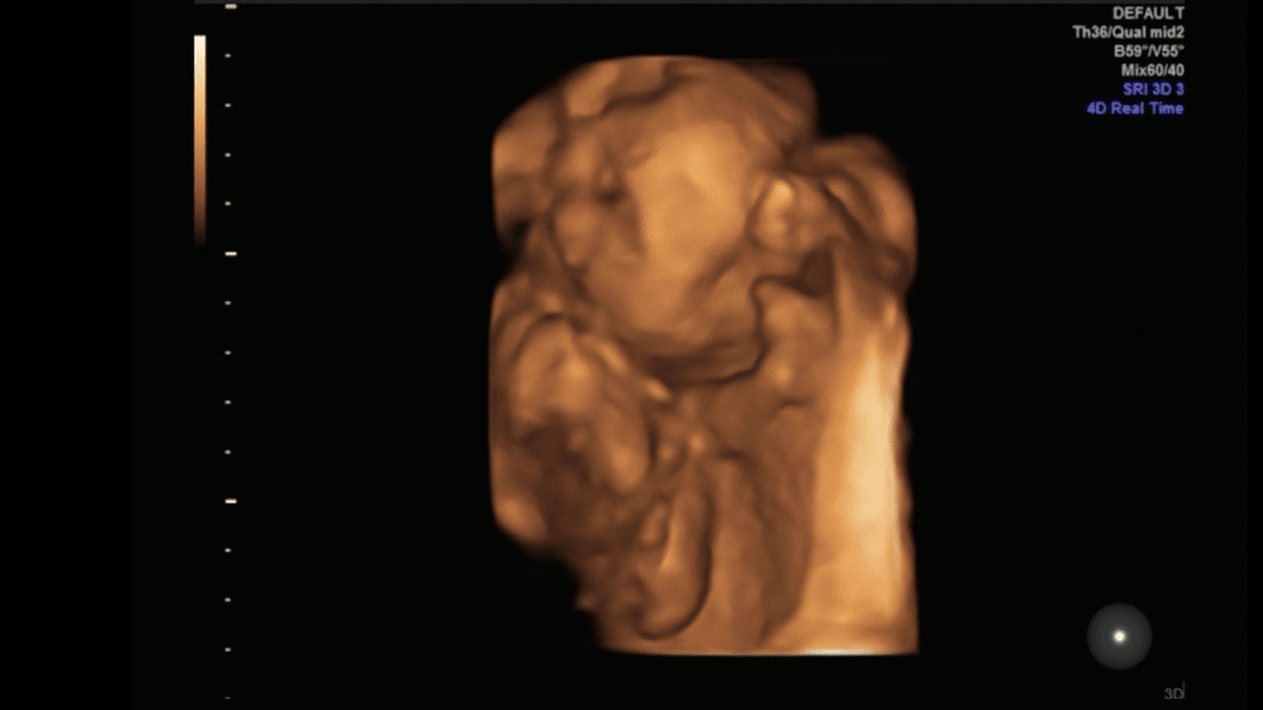

Wrzucę kilka fotek tutaj a resztę w wątku z usg

Nasz akrobata (stopa przy nosku)Zobacz załącznik 839724

Zobacz załącznik 839725

Stópki [emoji7]

O jejku jak ślicznie , a na tym drugim chyba sobie ziewa co

Tak akurat ziewałO jejku jak ślicznie , a na tym drugim chyba sobie ziewa co